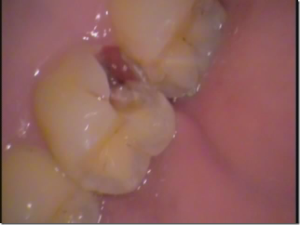

このセメントは歯をあまり削らずに治療ができるという特長があります。

虫歯が神経に近くまで達しているような場合や、なかなか痛みが治らない根の病気などにも効果があります。

セメントの材料の中の銅イオンが虫歯の部分を殺菌し再石灰化させ、治癒に向かわせます。

神経を抜かなくてはならないような虫歯では、ドグスベストセメントを使用した治療を行います。